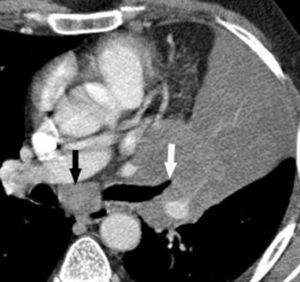

Valoración del tumor

La diferenciación entre tumores T3 y T4 puede ser difícil empleando sólo técnicas de imagen. Cuando se evidencia destrucción ósea (costal o vertebral), existe masa en el espacio intercostal (fig. 3), o las estructuras mediastínicas están claramente englobadas por el tumor, el diagnóstico es obvio (fig. 2). Sin embargo, sin estos hallazgos, la predicción de invasión es mucho menos fiable. Se han descrito diferentes signos que pueden ayudar a determinar la invasión de pared torácica. Éstos incluyen el contacto con la superficie pleural mayor de 3 cm, el engrosamiento pleural, la ausencia de plano graso y la presencia de un ángulo obtuso entre el tumor y la pared torácica. Aplicando al menos dos de estos criterios la sensibilidad es de un 87%, sin embargo la especificidad es baja (59%)4. El dolor torácico localizado es un síntoma importante que a menudo está asociado a invasión de pared.

Fig. 2.--T4. (A) Corte axial de tomografía computarizada (TC) torácica con contraste. Tumor hiliar derecho que infiltra la arteria pulmonar derecha, la vena cava superior y engloba al bronquio intermediario. (B) Reconstrucción coronal oblicua, longitudinal al eje de la arteria pulmonar derecha, que muestra cómo engloba el tumor a la rama del truncus superior (flecha blanca) e inferior (flecha negra).